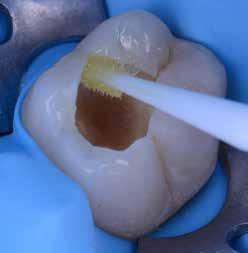

Az 53 éves hölgy páciens jobb felső 6-os fogában látható amalgámtömés cseréje volt a cél. A tömés mellett secunder caries és az amalgám következtében létrejött mesialis zárólécen áthaladó repedés, továbbá mesialis caries figyelhető meg (1. ábra). El kellett kerülni, hogy a tömés kifúrásakor az amalgámtörmelék a páciens szájába kerüljön, esetleg ebből valamennyit lenyeljen, a kezelés első lépésként kofferdám izoláció került fel a jobb felső kvadránsba (2. ábra). A kapocs a 1.7 fogra került, ezzel kényelmesen helyet teremtett a későbbiekben felkerülő matricarendszernek. Az egyszerre több fog izolálása lehetővé teszi, hogy a szomszédos fogak referenciául szolgáljanak a restauráció felépítése közben.

A régi amalgámtömés eltávolítását követően caries indikátor segítette a carieses laesio megfelelő kitisztítását a pulpa expozíciója nélkül. Ezután kerülhetett sor az ideális üregdesign kialakítására, továbbá a zománcszélek finírozására (3. ábra) Az approximális box megnyitása során az alátámasztatlan zománcprizmák eltávolításra kerültek, ezzel is csökkentve a secunder caries képződés veszélyét. Az így kialakuló forma elősegíti a matrica megfelelő adaptációját, végül pedig az approximális box határainak a hozzáférhetőségét, így finírozás során ez jobban kontrollálható és polírozható.

A Palodent V3 matricarendszer felhelyezését követően a zománc 10 másodperces szelektív savazása, majd lemosása és leszárítása után történt a kavítás bondozása Prime & Bond Universallal.

Kulcslépés: a II. osztályú üreget a matricarendszer segítségével I. osztályúvá lehetett átalakítani.

A pontosabb széli záródás érdekében célszerű a matrica illesztési határába némi folyékony kompozitot felvinni (NeoSpectra ST flow A2), majd megvilágítás nélkül a zárólécet paszta kompozittal (NeoSpectra STHV A2) felépíteni, miközben a kifolyó fölösleges folyékony kompozit eltávolításra kerülhet. Így ki lehetett használni és kombinálni a két különböző konzisztencia előnyeit.

A polimerizációt követően kerülhet sor a matricafeszítő gyűrű, valamint a matrica eltávolítására. A Palodent V3 fülekkel ellátott matrica kialakításának és a speciális PinTweezers csipesznek hála, a feszes kontaktpont ellenére a matrica könnyedén eltávolítható. Az éket viszont a kezelés végéig

célszerű bennhagyni, elkerülve egy esetleges nemkívánatos vérzést (4. ábra)

A matrica és gyűrű nélkül az approximális fal magassága, valamint a szomszédos fogakhoz viszonyítható dimenziók jobban megállapíthatóak. A jobb térlátás és a nagyobb mozgástér precízebb eredményhez vezet, csökkentve ezzel az utólagos finírozás mértékét, továbbá a részletgazdagon kialakított anatómiai struktúrák torzulásának az esélyét. Az üreg mélyebb részei SDR Plus A3-mal kerültek feltöltésre, majd NeoSpectra STLV A3-mal kiegészítve vált teljessé a dentin pótlása (5. ábra), ezzel létre lehetett hozni egy homorú formájú kromatikusabb alapot.

Ezt követően csücsökről csücsökre haladva a felső hatosokra jellemző anatómiai struktúrák, megfelelő orientációval bíró csücsöklejtők és elsődleges barázdák Neo Spectra

HV A2 anyagból kerültek kialakításra (6. ábra). Apró „kompozit-hurkákkal” kiegészítve létrehozható a csücskökön belüli tagoltság, ezzel kialakítva a másodlagos barázdarendszert és egy sokkal kidolgozottabb anatómiai struktúrát (7. ábra). A fogorvos esetleges „művészi hajlamát” is figyelembe véve, a természethű megjelenés barázdafestéssel (Micerium - Stain Brown 2) még tökéletesebb lehet (8. ábra). Ezzel a korábban részletgazdagon kialakított ba-